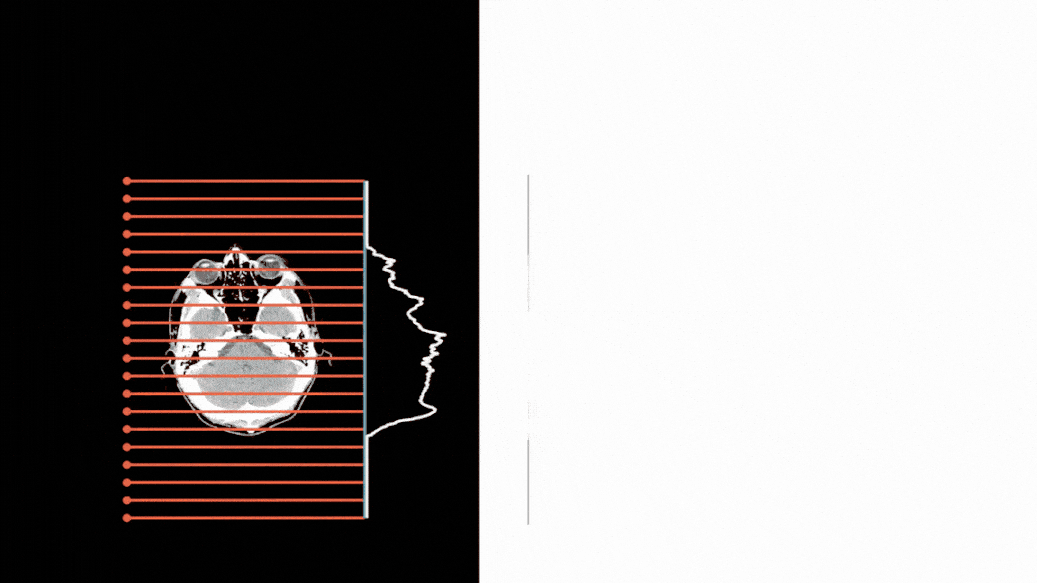

TL;DR: Comprehensive benchmarking and challenge for deep learning and classical methods in low-dose 3D cone-beam CT reconstruction, using realistic simulations and clinical data.

TL;DR: SwinIR-based sinogram and image enhancement modules significantly improve 3D CBCT reconstruction, ranking among the top 5 solutions in the 2024 challenge.